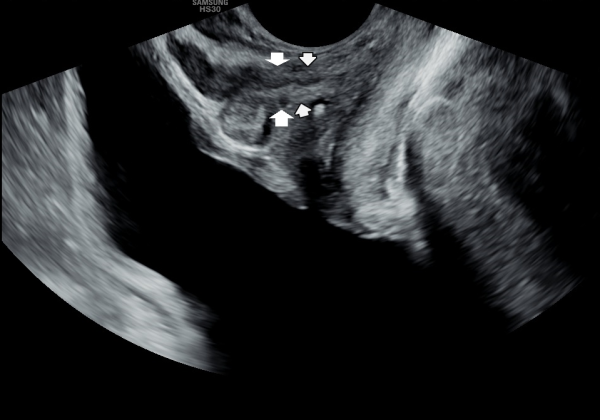

환자분의 개인 사정상 주 1회 가량 전립선의 표적 치료를 한후 탈락된 상피세포가 사정관 입구와 사정관에내에 참착되어 추적 경직장 전립선의 초음파 검사상 석회가 관찰되는 자료입니다.

Due to the patient's personal circumstances, targeted prostatic therapy was performed approximately once a week. As a result, exfoliated epithelial cells became deposited at the ejaculatory duct orifice and within the ejaculatory duct, and calcifications were observed on follow-up transrectal prostate ultrasound imaging.